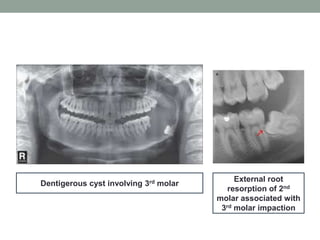

• Dentigerous cyst formation: Other related pathologies

which expand the bone and results in pathological

fracture.

• External resorption of the second molar: Caused by

the pressure of the third molar on 2nd molar.

Dentigerous cyst involving 3rd molar

External root

resorption of 2nd

molar associated with

3rd molar impaction

Dentigerous cyst involving3rd molar External root resorption of 2nd molar associated with 3rd molar impaction